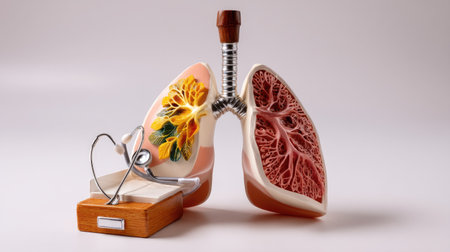

Anatomical model of human lungs featuring vivid colors and intricate patterns, highlighting the complexity of the respiratory system in an educational display.